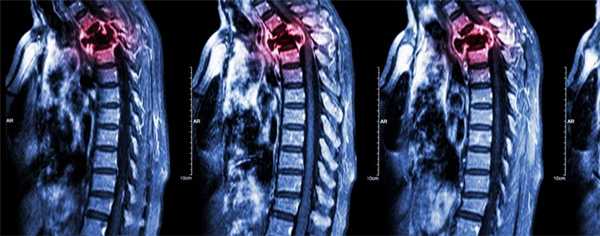

Система оценки распространения опухолей Weinstein-Boriani-Biagini,

используемая при планировании их радикальной резекции «единым блоком». Резекция опухоли, межтеловой спондилодез кейджем и задняя стабилизация по поводу опухоли Т7,

оцененной по системе Tokuhashi выше 13. Рентгенограммы в боковой (слева) и прямой (справа) проекциях после корпорэктомии Т7 и стабилизации грудного отдела позвоночника.